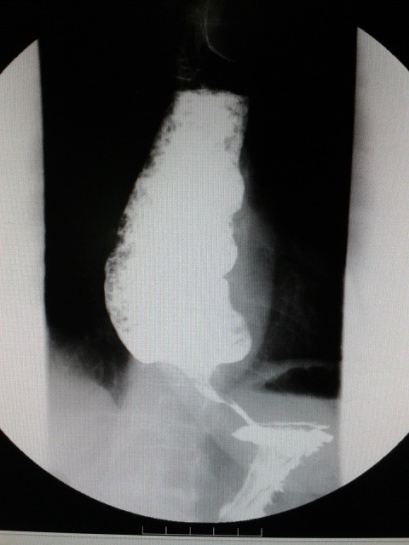

消化科成功对Heller手术失败的贲门失弛缓症患者实施POEM术

近日,消化科成功对两位Heller手术失败的贲门失弛缓症患者实施通过经口内镜下肌切开术(POEM)术。 其中一位患者支女士,吞咽困难18年,11年前外院明确诊断为贲门失迟缓症,进行了贲门食管肌层切开术(Heller),术后吞...